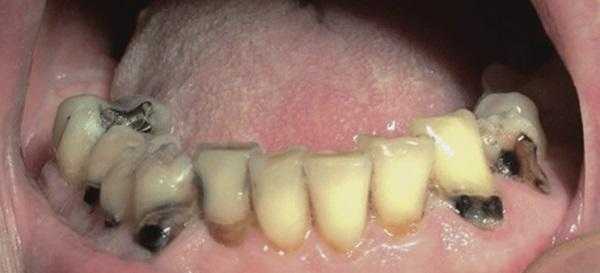

При уменьшенном слюноотделении слизистая оболочка полости рта становиться сухой и в ходе диагностике к ней могут прилипать перчатки, валики и даже стоматологические зеркала. На спине языка могут визуализироваться нитевидные сосочки и трещины, наличие которых позволяет поставить диагноз волосатого языка (фото 1). В пришеечных областях зуба часто визуализируются участки кариозного поражения (фото 2), небольшие эритематозные пятна диагностируются на слизистой щеки, где также могут присутствовать следы накусывания от зубов (фото 3). У пациентов также могут отмечаться признаки гингивита, рецессии и пародонтита (фото 4).

Фото 2. Кариозные и сопутствующие поражения у пациента с ксеростомией.

Также при ксеростомии возникают новые и рецидивируют существующие участки кариозного поражения, при этом пожилые пациенты являются наиболее уязвимыми к подобным осложнениям, поскольку большее количество их собственных зубов уже подвергалось стоматологическому лечению, а в пришеечной области таковых часто наблюдаются участки рецессии десен. Особенно часто рецессии возникают со щечной поверхности ранее восстановленных фронтальных зубов (фото 1).

Фото 1. Вид полости рта пациента с острыми кариозными поражениями вестибулярных и пришеечных поверхностей зубов, вызванные долгосрочным приемом антихолинергических препаратов.